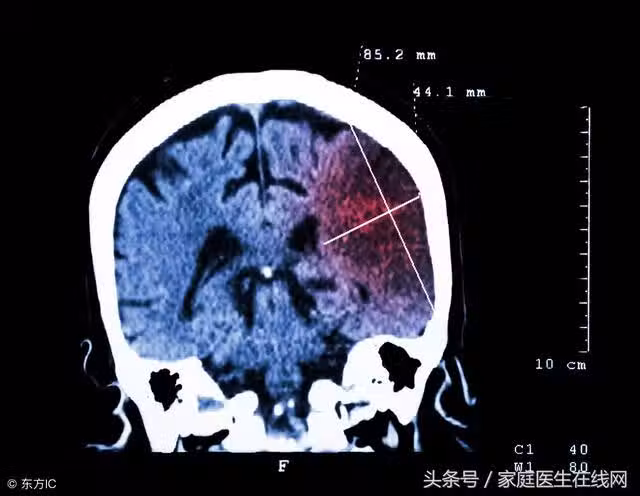

腦梗多發於中老年人,其致死率和致殘率都很高。除此之外,腦梗還容易反覆發作,這對患者的影響更是難以言喻。那麼為什麼腦梗會反覆發作呢?患者怎樣做才能有效防治腦梗發作?下面,讓我們一起來了解一下。